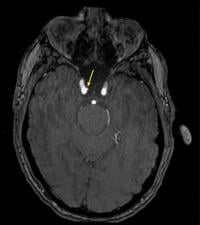

Representative axial time-of-flight MR angiography image in a 39-year-old male participant shows a laterally projecting intracranial aneurysm (arrow) originating from the right cavernous segment of the internal carotid artery. (RSNA via SWNS)

De Giorgi said: "Intracranial aneurysms were three times more common in highly exposed personnel.

"Even after accounting for other health factors such as age and blood pressure, the association remained significant.

Representative axial time-of-flight MR angiography image in a 35-year-old male participant shows a medially projecting intracranial aneurysm (arrow) originating from the right cavernous segment of the internal carotid artery. (RSNA via SWNS)

"These findings suggest that repeated blast exposure may leave a measurable vascular signature in the brain."